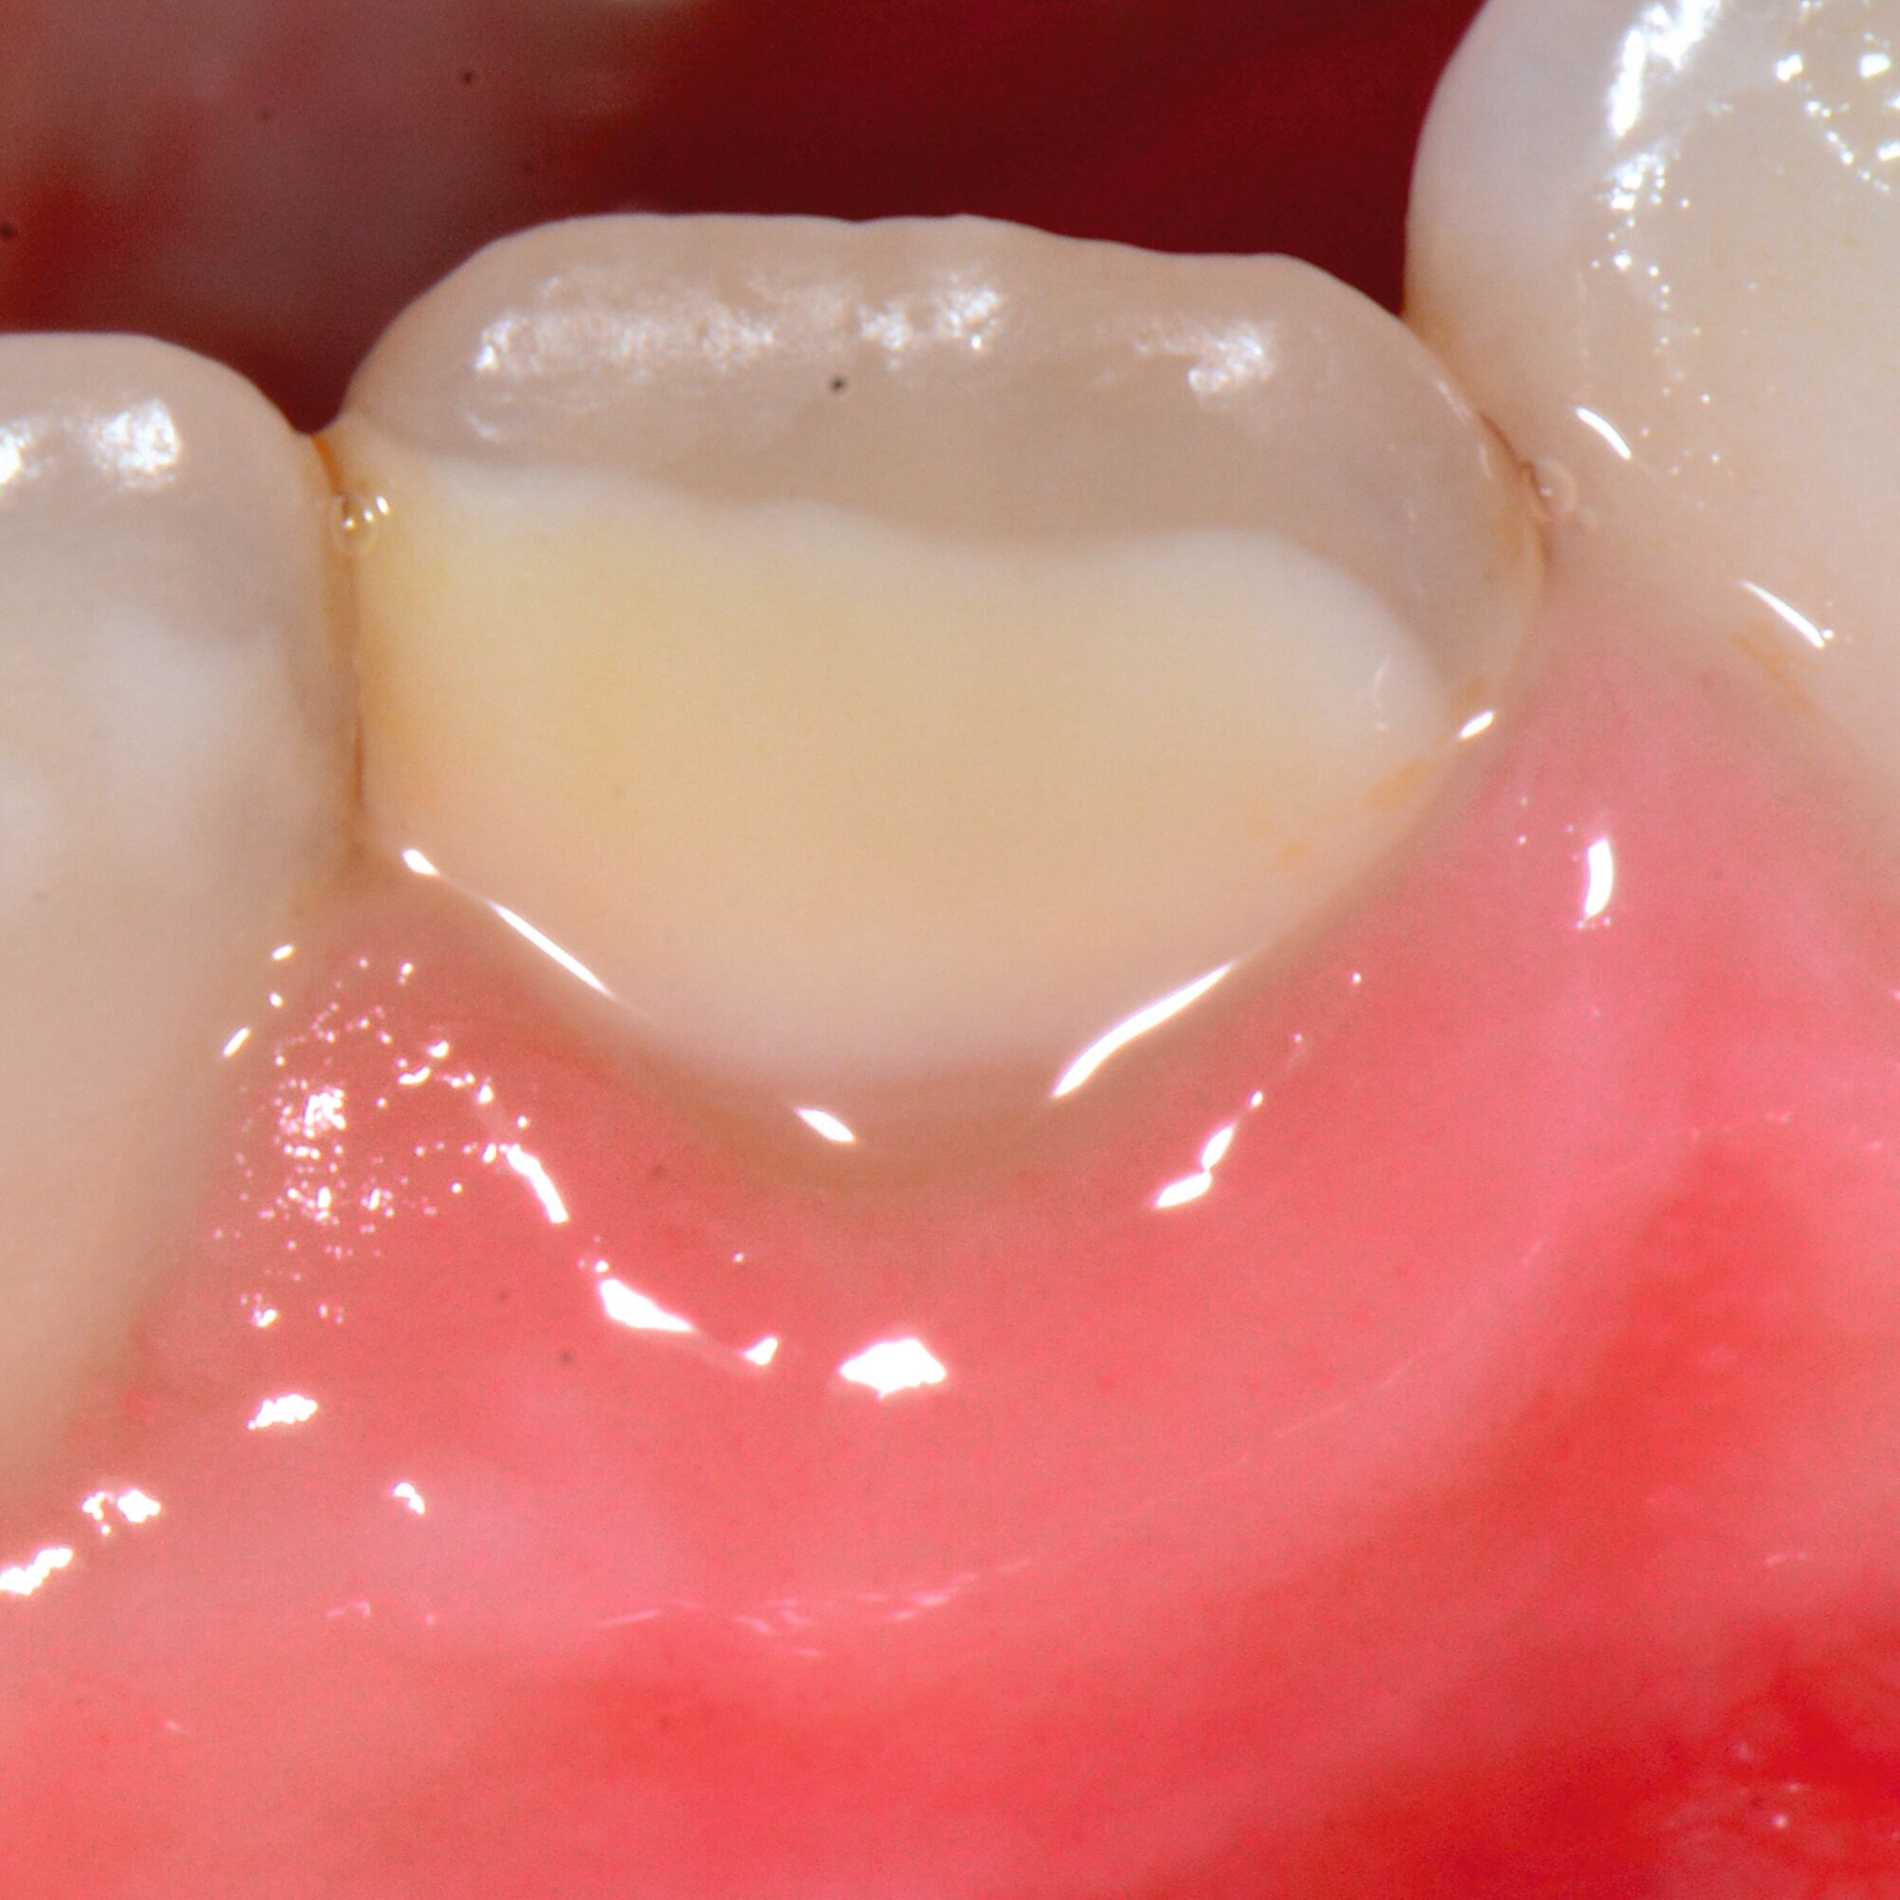

An umfangreich hypomineralisierten Zähnen können Schmelzeinbrüche (engl.: „enamel breakdown“ oder „enamel desintegration“, Abbildung 5) auftreten [Lygidakis et al., 2010; 2022]. Da diese oftmals die Folge einer fehlenden Belastungsfähigkeit des Zahnschmelzes sind und erst nach der Einstellung der Zähne in die Okklusion auftreten, werden sie auch als posteruptive Schmelzeinbrüche bezeichnet. Sie sind häufig im Bereich der Kauflächen beziehungsweise Höcker der Molaren zu finden, führen zur Dentinexposition und damit einhergehend zu ausgeprägten Hypersensitiven insbesondere bei Kindern, deren Zähne gerade erst durchgebrochen sind [Linner et al., 2021].

Frontzähne sind seltener von MIH-bedingten Schmelzeinbrüchen und Hypersensitivitäten betroffen. Von den posteruptiven Oberflächeneinbrüchen sind präeruptive Defekte abzugrenzen. Diese Zähne brechen bereits mit einem vorhandenen Oberflächendefekt in die Mundhöhle durch.